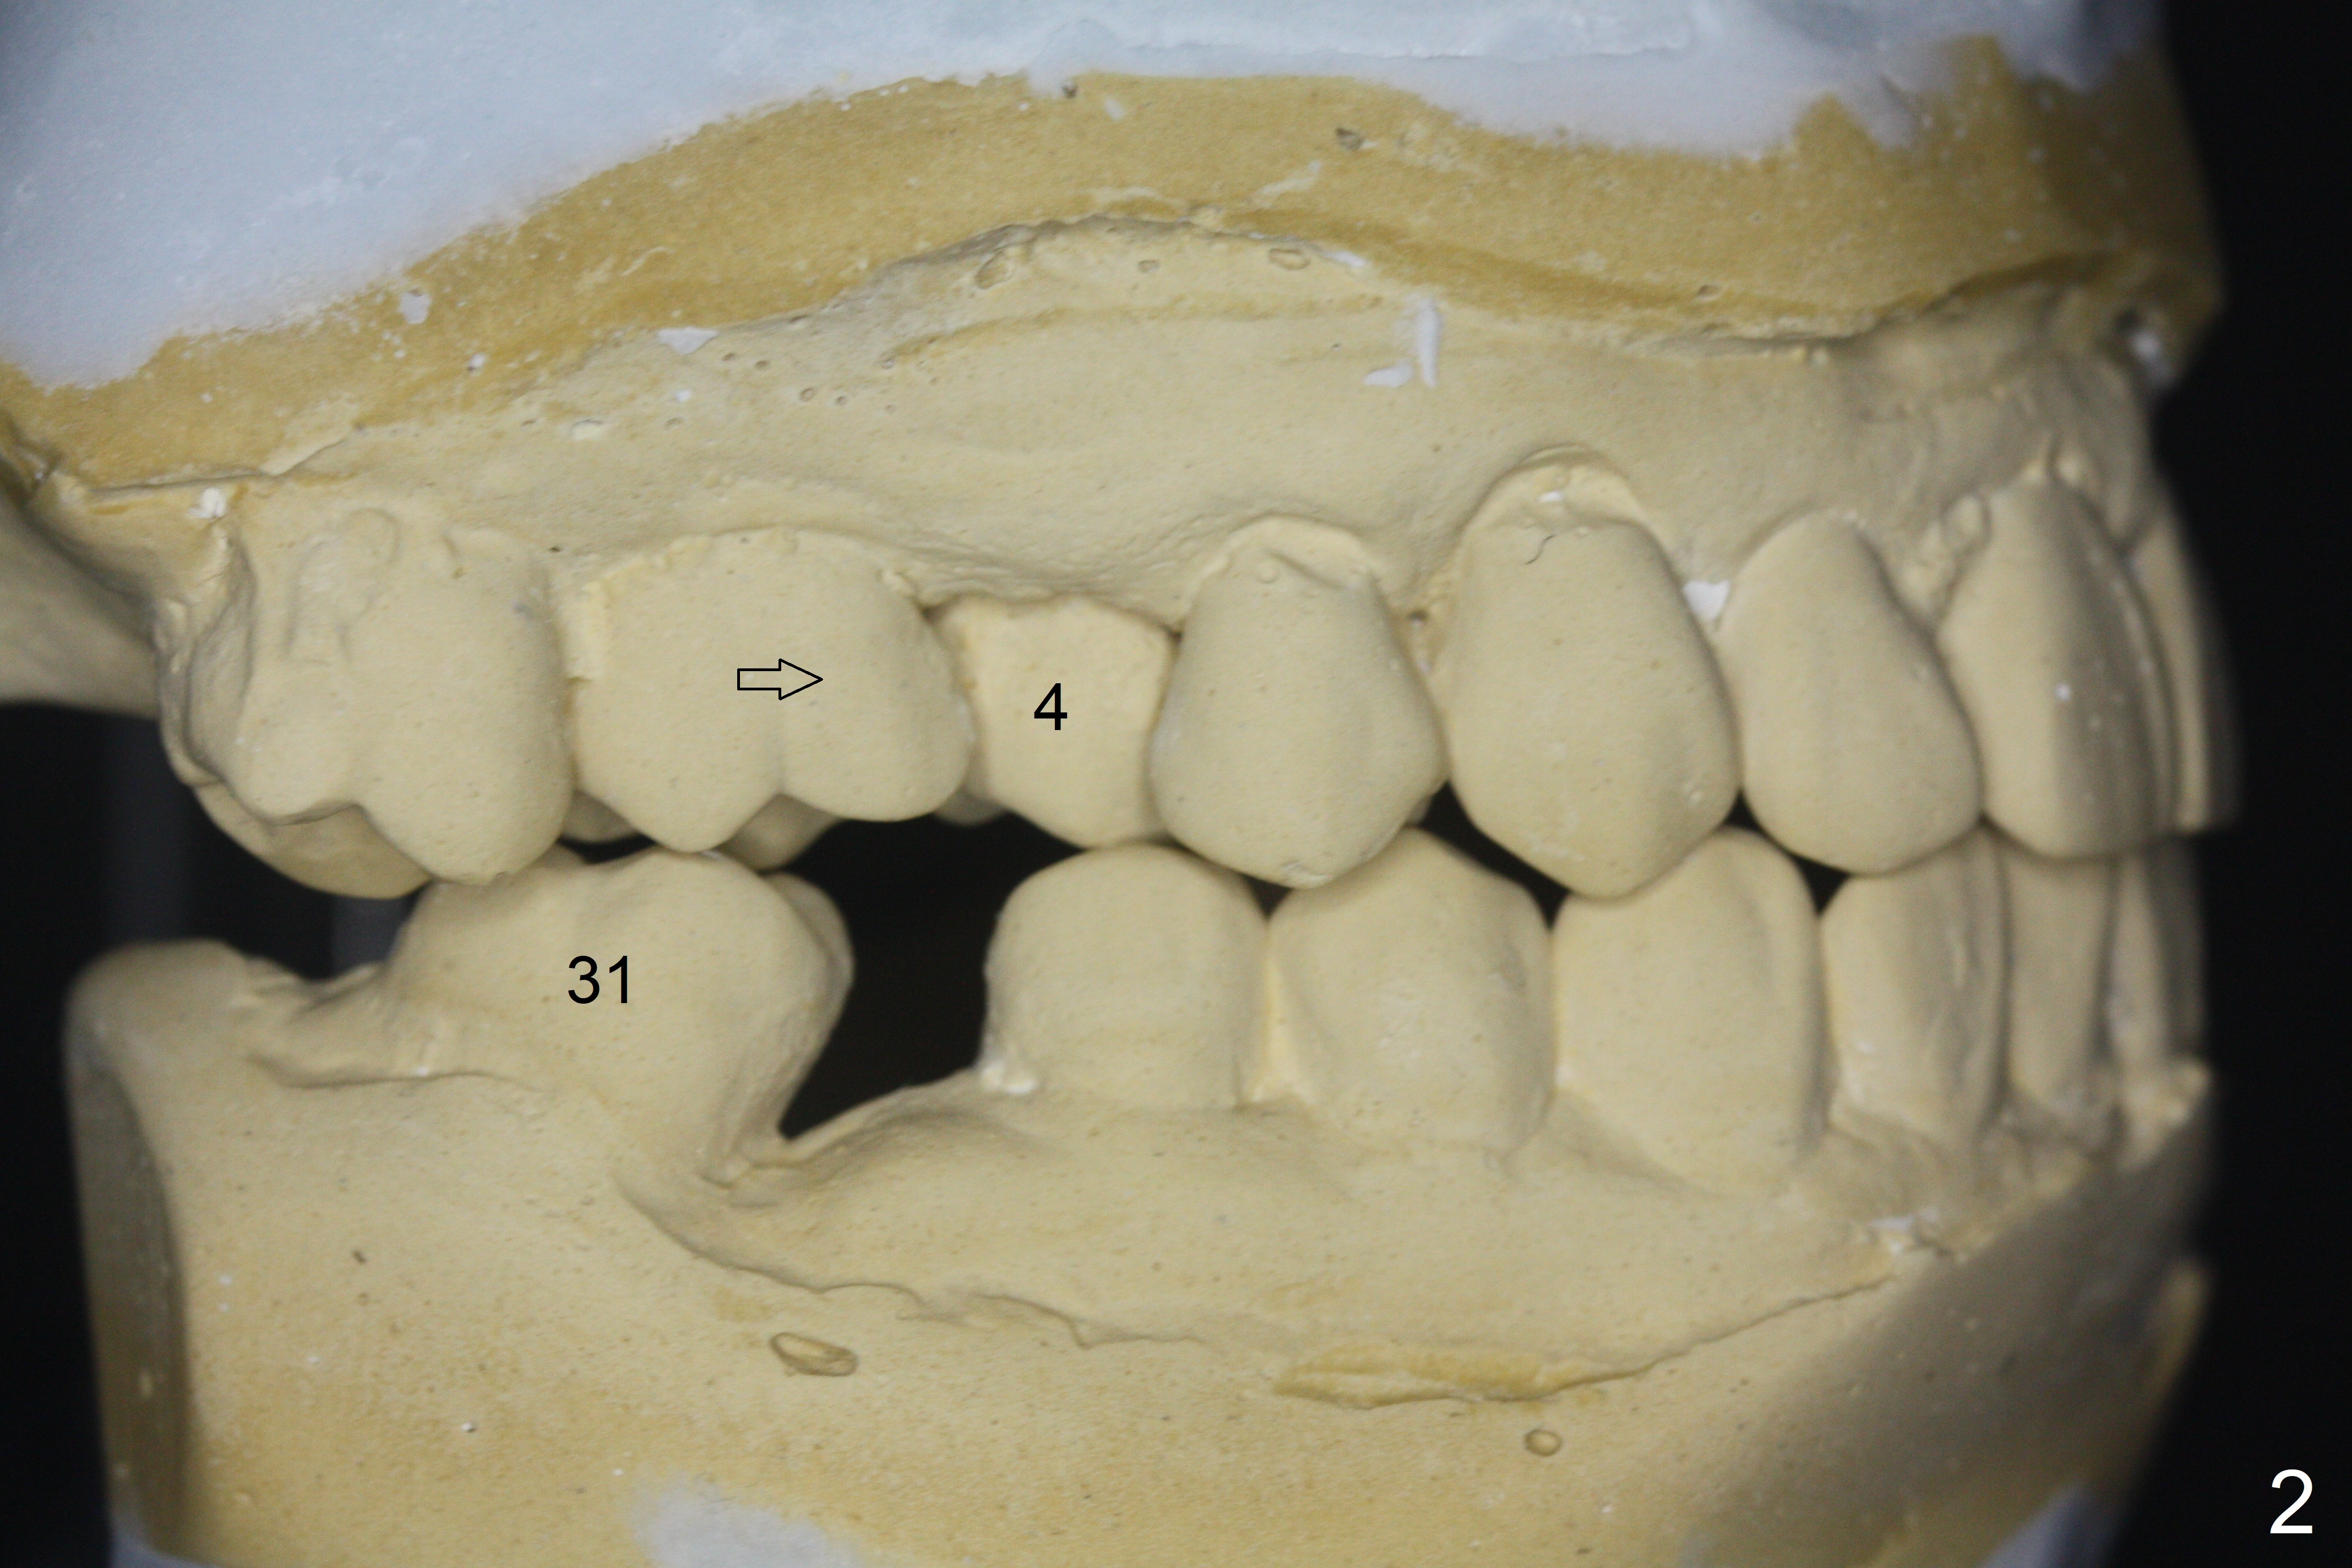

A 64-year-old man has discomfort with the lower left bridge and a loose tooth on the left (Fig.1). It appears that 4 implants are to be placed at #18,19,30 and 31. Since the tooth #4 and 13 are palatalized (Fig.2-4), the teeth #2 and 3 are mesialized (Fig.2 arrow). Besides, the ridge at #30 must be atrophic due to long termed edentulism. A small-diameter implant will be placed at #30 with premolar width (Fig.6-13), while the implant at #31 will be placed distal (arrow, as compared to Fig.2). To establish harmonious occlusion at provisional and final stages, the palatal slope of the mesiopalatal cusp of the tooth #2 will be adjusted (Fig.10).